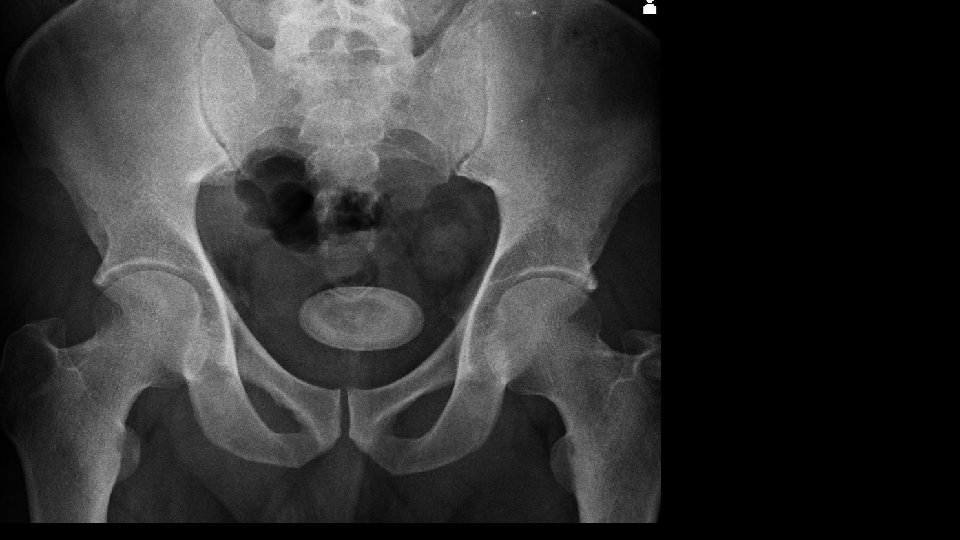

Urolithiasis Calculi along urinary tract • Anywhere • Kidney • Ureter • Bladder